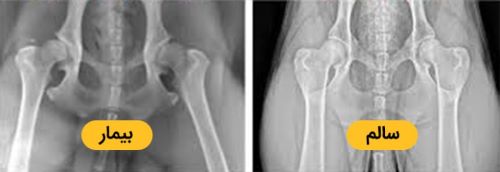

2-بیماری دیسپلازی هیپ در سگ ها

یکی از بیماری های ارثی و ژنتیکی در سگ ها دیسپلازی مفصل ران است؛ در واقع این بیماری در عملکرد مفصل ران تاثیر گذاشته و مهمترین نتیجه اش میشه لنگیدن و درد کشیدن حیوان.

Hip Dysplasia بیش تر در کمین سگ های بزرگه و در نژادهای گلدن رتریور، گریت دین، ماستیف، باکسر، ژرمن شپرد دیده میشه و زندگی حیوان رو تحت تاثیر قرار میده؛ حواست باشه که اگه نسبت به درمانش اقدام نکنی منجر به آرتروز میشه هاااا!!!...